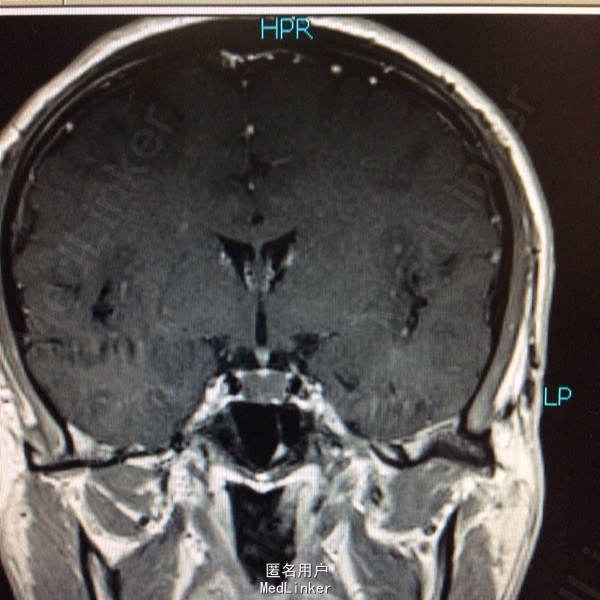

男性,31岁,头痛起病,无恶心呕吐,无视力改变。

查体未见明显阳性体征,发育正常 头颅CT提示鞍区少量出血 MRI增强提示鞍区占位病变,大小约0.8*1.5cm 考虑垂体瘤卒中

术前诊断:垂体瘤 择期行经蝶入路垂体瘤切除术 术后病理提示垂体腺瘤

讨论:卒中垂体瘤的手术时机选择?